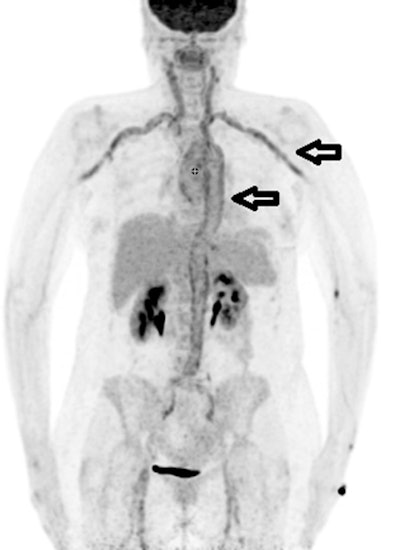

F-18 FDG PET/CT is effective for diagnosing fevers of unknown origin in more than half of cases after other imaging approaches have failed, according to a study published February 3 in Scientific Reports.

Austrian researchers analyzed the use of F-18 FDG PET/CT in patients who presented with fevers of unknown origin yet who remained undiagnosed despite other significant diagnostic efforts. They found F-18 FDG-PET/CT diagnosed causes in more than 50% of cases after other modalities failed, including chest x-ray, CT, MRI, and sonography.

The study results revealed that PET/CT was the decisive examination for establishing the final diagnosis in 54% of patients. F-18 FDG-PET/CT findings were equivocal and indecisive in 13.3% and false positive in 3.3%. A normal F-18 FDG pattern was present in 29.3% of patients.